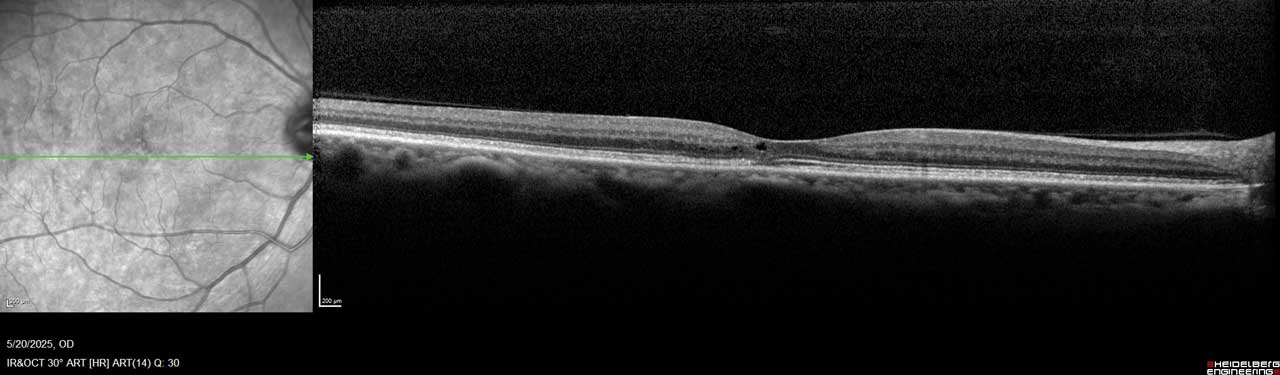

Figure 1. This image of the right eye of a patient with MacTel type 2 shows a hyporeflective inner retinal cavity and loss of outer retinal signals, including photoreceptors temporal to the center of the macula.

MacTel is believed to result from degeneration of Müller cells, the glial cells that surround and support neurons in the retina. This neurodegeneration leads to outer retinal atrophy and thinning, ultimately resulting in photoreceptor loss. In later stages, hyporeflective spaces in the outer retinal layer—most often within the foveal pit—can be observed on optical coherence tomography (OCT), indicating photoreceptor loss (Figure 1 and Figure 2).¹